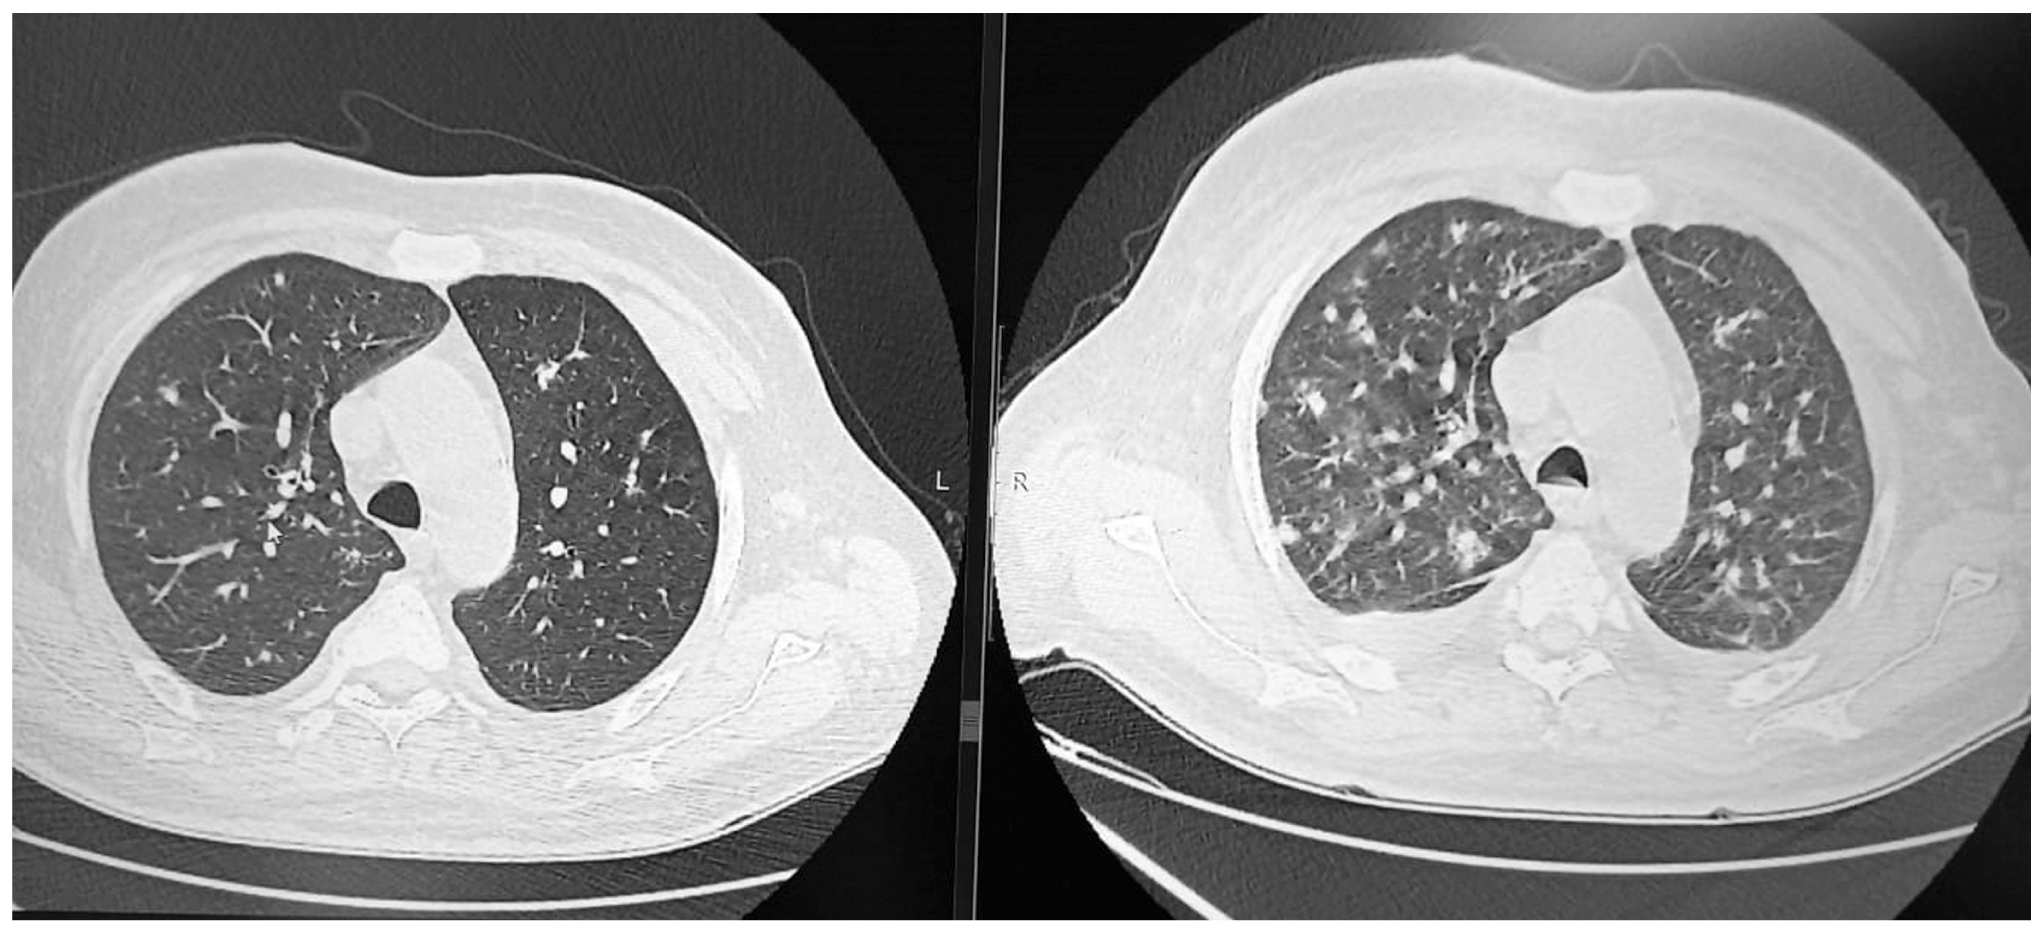

Повторная КТ ОГК от 08.02.2021: справа и слева во всех сегментах лёгких множество полиморфных очагов (рис. 2, слева). Увеличение подмышечных лимфатических узлов до 15×7 мм.

Назначена противотуберкулёзная терапия (ПТТ) изониазидом, рифабутином, этамбутолом, пиразинамидом. Продолжены профилактика пневмоцистной пневмонии (ко-тримоксазол в дозе 480 мг в сутки) и АРВТ по прежней схеме. На фоне ПТТ развились симптомы токсического гепатита, появилась отёчность периорбитальной области. После назначения инфузионной терапии, гепатопротекторов, сорбентов явления токсического гепатита уменьшились. С 19.02.2021 к терапии добавлен ганцикловир в дозе 5 мг/кг 2 раза в сутки. Однако, несмотря на ПТТ и прием ганцикловира, сохранялась лихорадка на фебрильных цифрах. Повторная КТ ОГК от 26.02.2021 выявила увеличение количества очагов в нижних отделах, а также жидкость в плевральных полостях с обеих сторон (рис. 2, справа). Рентгенологическая картина расценена в пользу поражения лёгких СК в сочетании с пневмонией, вызванной ЦМВ. После получения данных КТ ОГК, а также в связи с отсутствием клинического и рентгенологического эффекта ПТТ была отменена. На 12-й день лечения ганцикловиром у пациента вновь появились симптомы токсического гепатита, печёночно-клеточной недостаточности (снижение протромбинового индекса до 70%, гипербилирубинемия до 59 мкмоль/л, в том числе 10 мкмоль/л за счёт прямого билирубина, повышение показателей цитолиза: АЛТ — 100 ЕД/л, АСТ — 89 ЕД/л), а также развилась лейкопения до 1,9×109/л, анемия средней степени тяжести (Hb — 85 г/л) и тромбоцитопения до 127×109/л. В связи с развитием печёночно-клеточной недостаточности, панцитопении было принято решение отменить ганцикловир и ко-тримоксазол. АРВТ пациент продолжал принимать. На фоне дезинтоксикационной инфузионной терапии у пациента отмечалось улучшение самочувствия и показателей общего анализа крови и функциональных проб печени, однако было отмечено снижение CD4-лимфоцитов до уровня 23 клеток/мкл. Также стало заметным прогрессирование внешних признаков СК: появились новые элементы, увеличились в размерах уже имеющиеся узлы.

Рис. 2. Результаты КТ ОГК от 08.02.2021 (слева) и 26.02.2021 (справа).

Fig. 2. The results of CT scan of the chest organs dated 08.02.2021 (left) and 26.02.2021 (right).